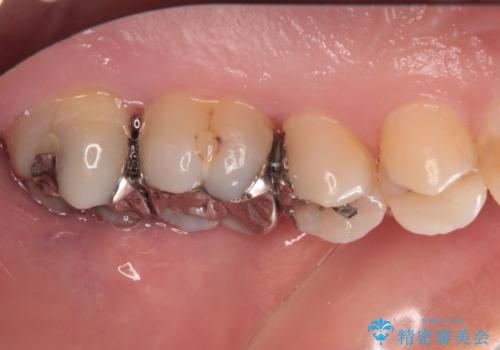

精度の高いセラミックインレーによる修復治療を行うこととしました。

処置を行った歯以外にもむし歯と思われる歯が多数ありますが、費用のかかる治療であれば、優先順位をつけて、処置を急ぐ歯から処置を進めて行きました。